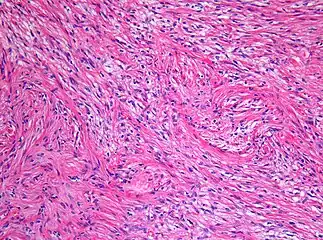

| Micrograph of a pilocytic astrocytoma, showing characteristic bipolar cells with long pilocytic (hair-like) processes. Smear preparation. H&E stain. | |

Under the microscope, the tumor is seen to be composed of bipolar cells with long "hair-like" GFAP-positive processes, giving the designation "pilocytic" (that is, made up of cells that look like fibers when viewed under a microscope[6]). Some pilocytic astrocytomas may be more fibrillary and dense in composition. The presence of Rosenthal fibers,[7] eosinophilic granular bodies, and microcysts can often be seen. Myxoid foci and oligodendroglioma-like cells may also be present, though these are not specific to pilocytic astrocytoma. Long-standing lesions may show hemosiderin-laden macrophages and calcifications.